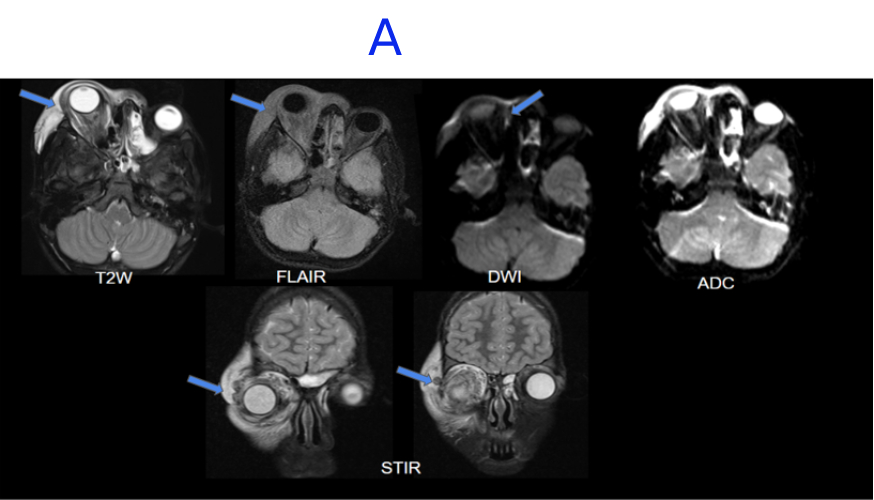

A. FINDINGS – MRI BRAIN WITHOUT IV CONTRAST - DAY 1

A. Right globe proptosis noted . There is extensive T2/STIR hyperintense edema noted in periorbital soft tissue and orbital compartments involving intraconal, extraconal and preseptal space. There is soft tissue stranding involving postseptal fat, surrounding the extraocular muscles and enlargement of lacrimal gland.There is a small diffusion restricting collection along medial wall of orbit. There is thrombophlebitis of an external vein along the superolateral superficial soft tissues.